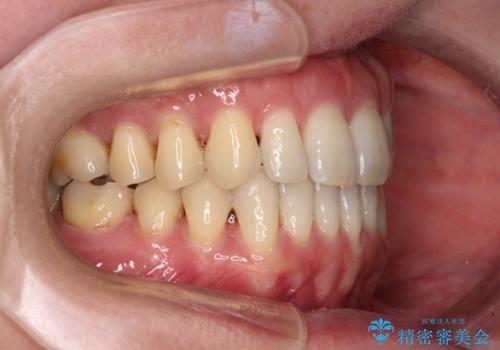

八重歯のインビザライン矯正治療

- 下顎の八重歯と、上下のクロスバイトを気にして来院された患者様です。

インビザラインを用い、下顎全体の後方移動、IPR(歯と歯の間を削る)と歯列全体を拡大させることで、歯並びを整えていくこととしました。